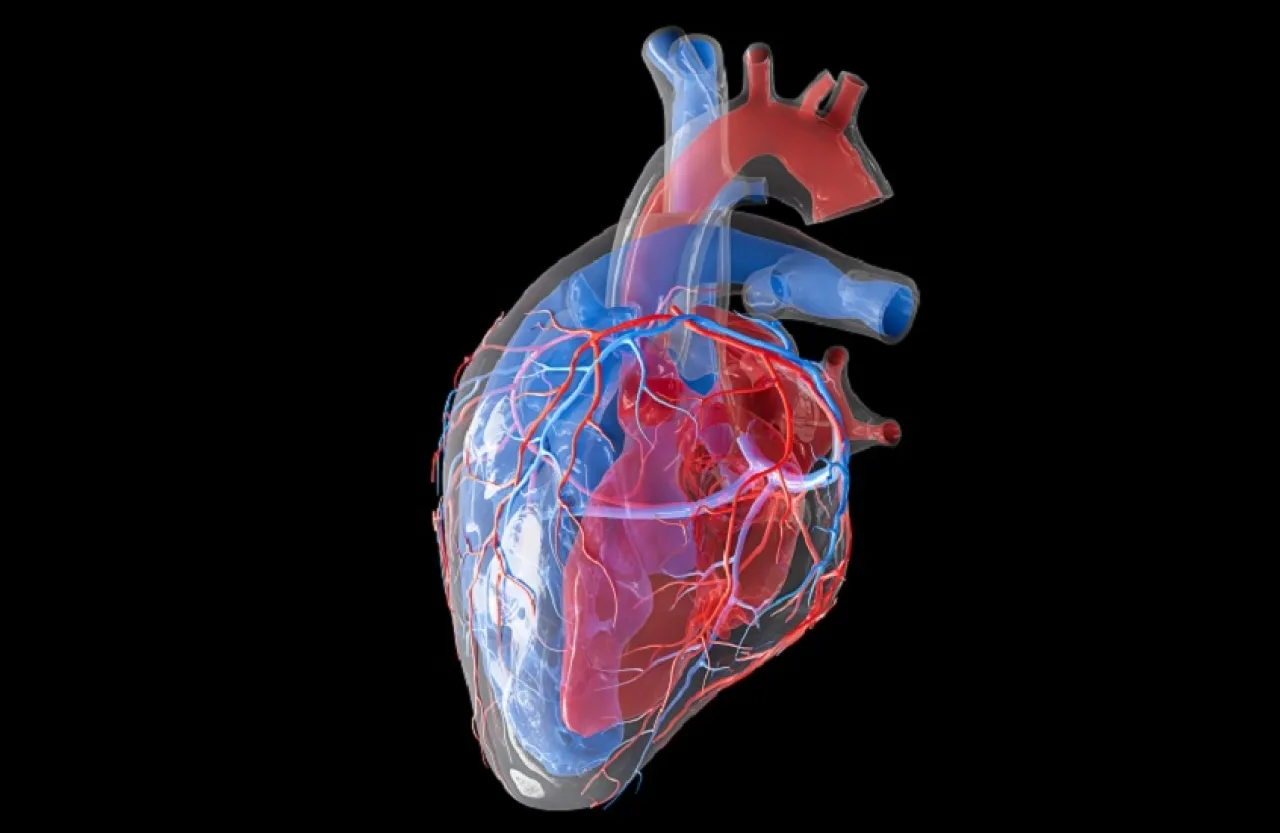

خبرني - أظهرت دراسات حديثة، أن تناول حبوب الشوفان من شأنه المحافظة على صحة القلب، مع التقدم في السن، بحسب صحيفة "ديلي ميل".

ويبرز الشوفان كأحد أفضل الأطعمة الداعمة لصحة القلب، بفضل غناه بالألياف القابلة للذوبان، خصوصًا "بيتا غلوكان"، التي ترتبط بالكوليسترول الضار داخل الجهاز الهضمي وتساعد على التخلص منه، مما ينعكس في خفض مستويات LDL في الدم.

كما يساهم الشوفان في تقليل أكسدة الكوليسترول الضار لاحتوائه على مضادات أكسدة طبيعية من نوع البوليفينولات، وهو ما يحد من تراكم اللويحات داخل الشرايين ويحمي القلب على المدى البعيد.

ومع المواظبة على تناوله دون إضافة السكريات، يمكن أن ينخفض الكوليسترول الضار تدريجيًا، ما يحسّن مرونة الشرايين ويقلل خطر انسدادها. في المقابل، فإن إضافة السكر أو الدهون المشبعة، مثل الزبدة أو زيت جوز الهند، قد تقلل من هذه الفوائد.

وتظهر البيانات أن كبار السن هم الأكثر عرضة للإصابة بأمراض القلب والسكتات الدماغية، إذ ترتفع النسب بشكل ملحوظ بعد سن 65 عامًا، وتزداد تدريجيًا مع التقدم في العمر.